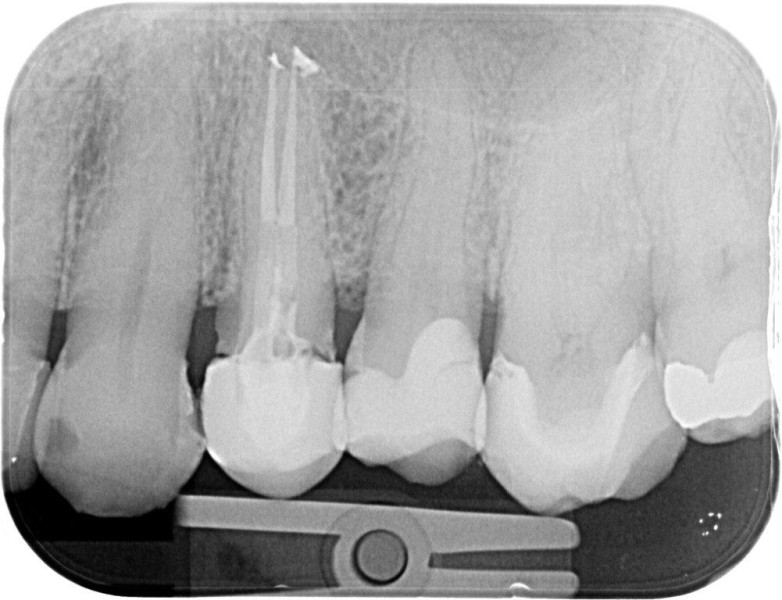

Molar retreatment